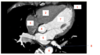

label 1

A

RV

2

Apex

Q

3

RA

17

4

LV

18

5

oesophagus

19

6

LA

20

7

aorta

21

8

azygos vein